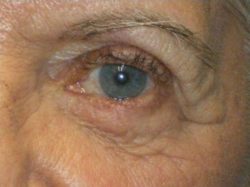

- Before/After